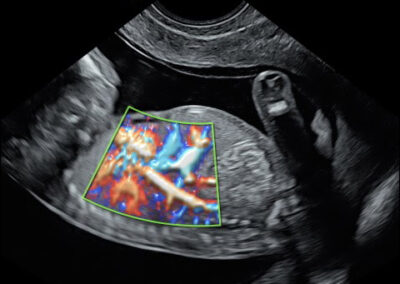

גלריה